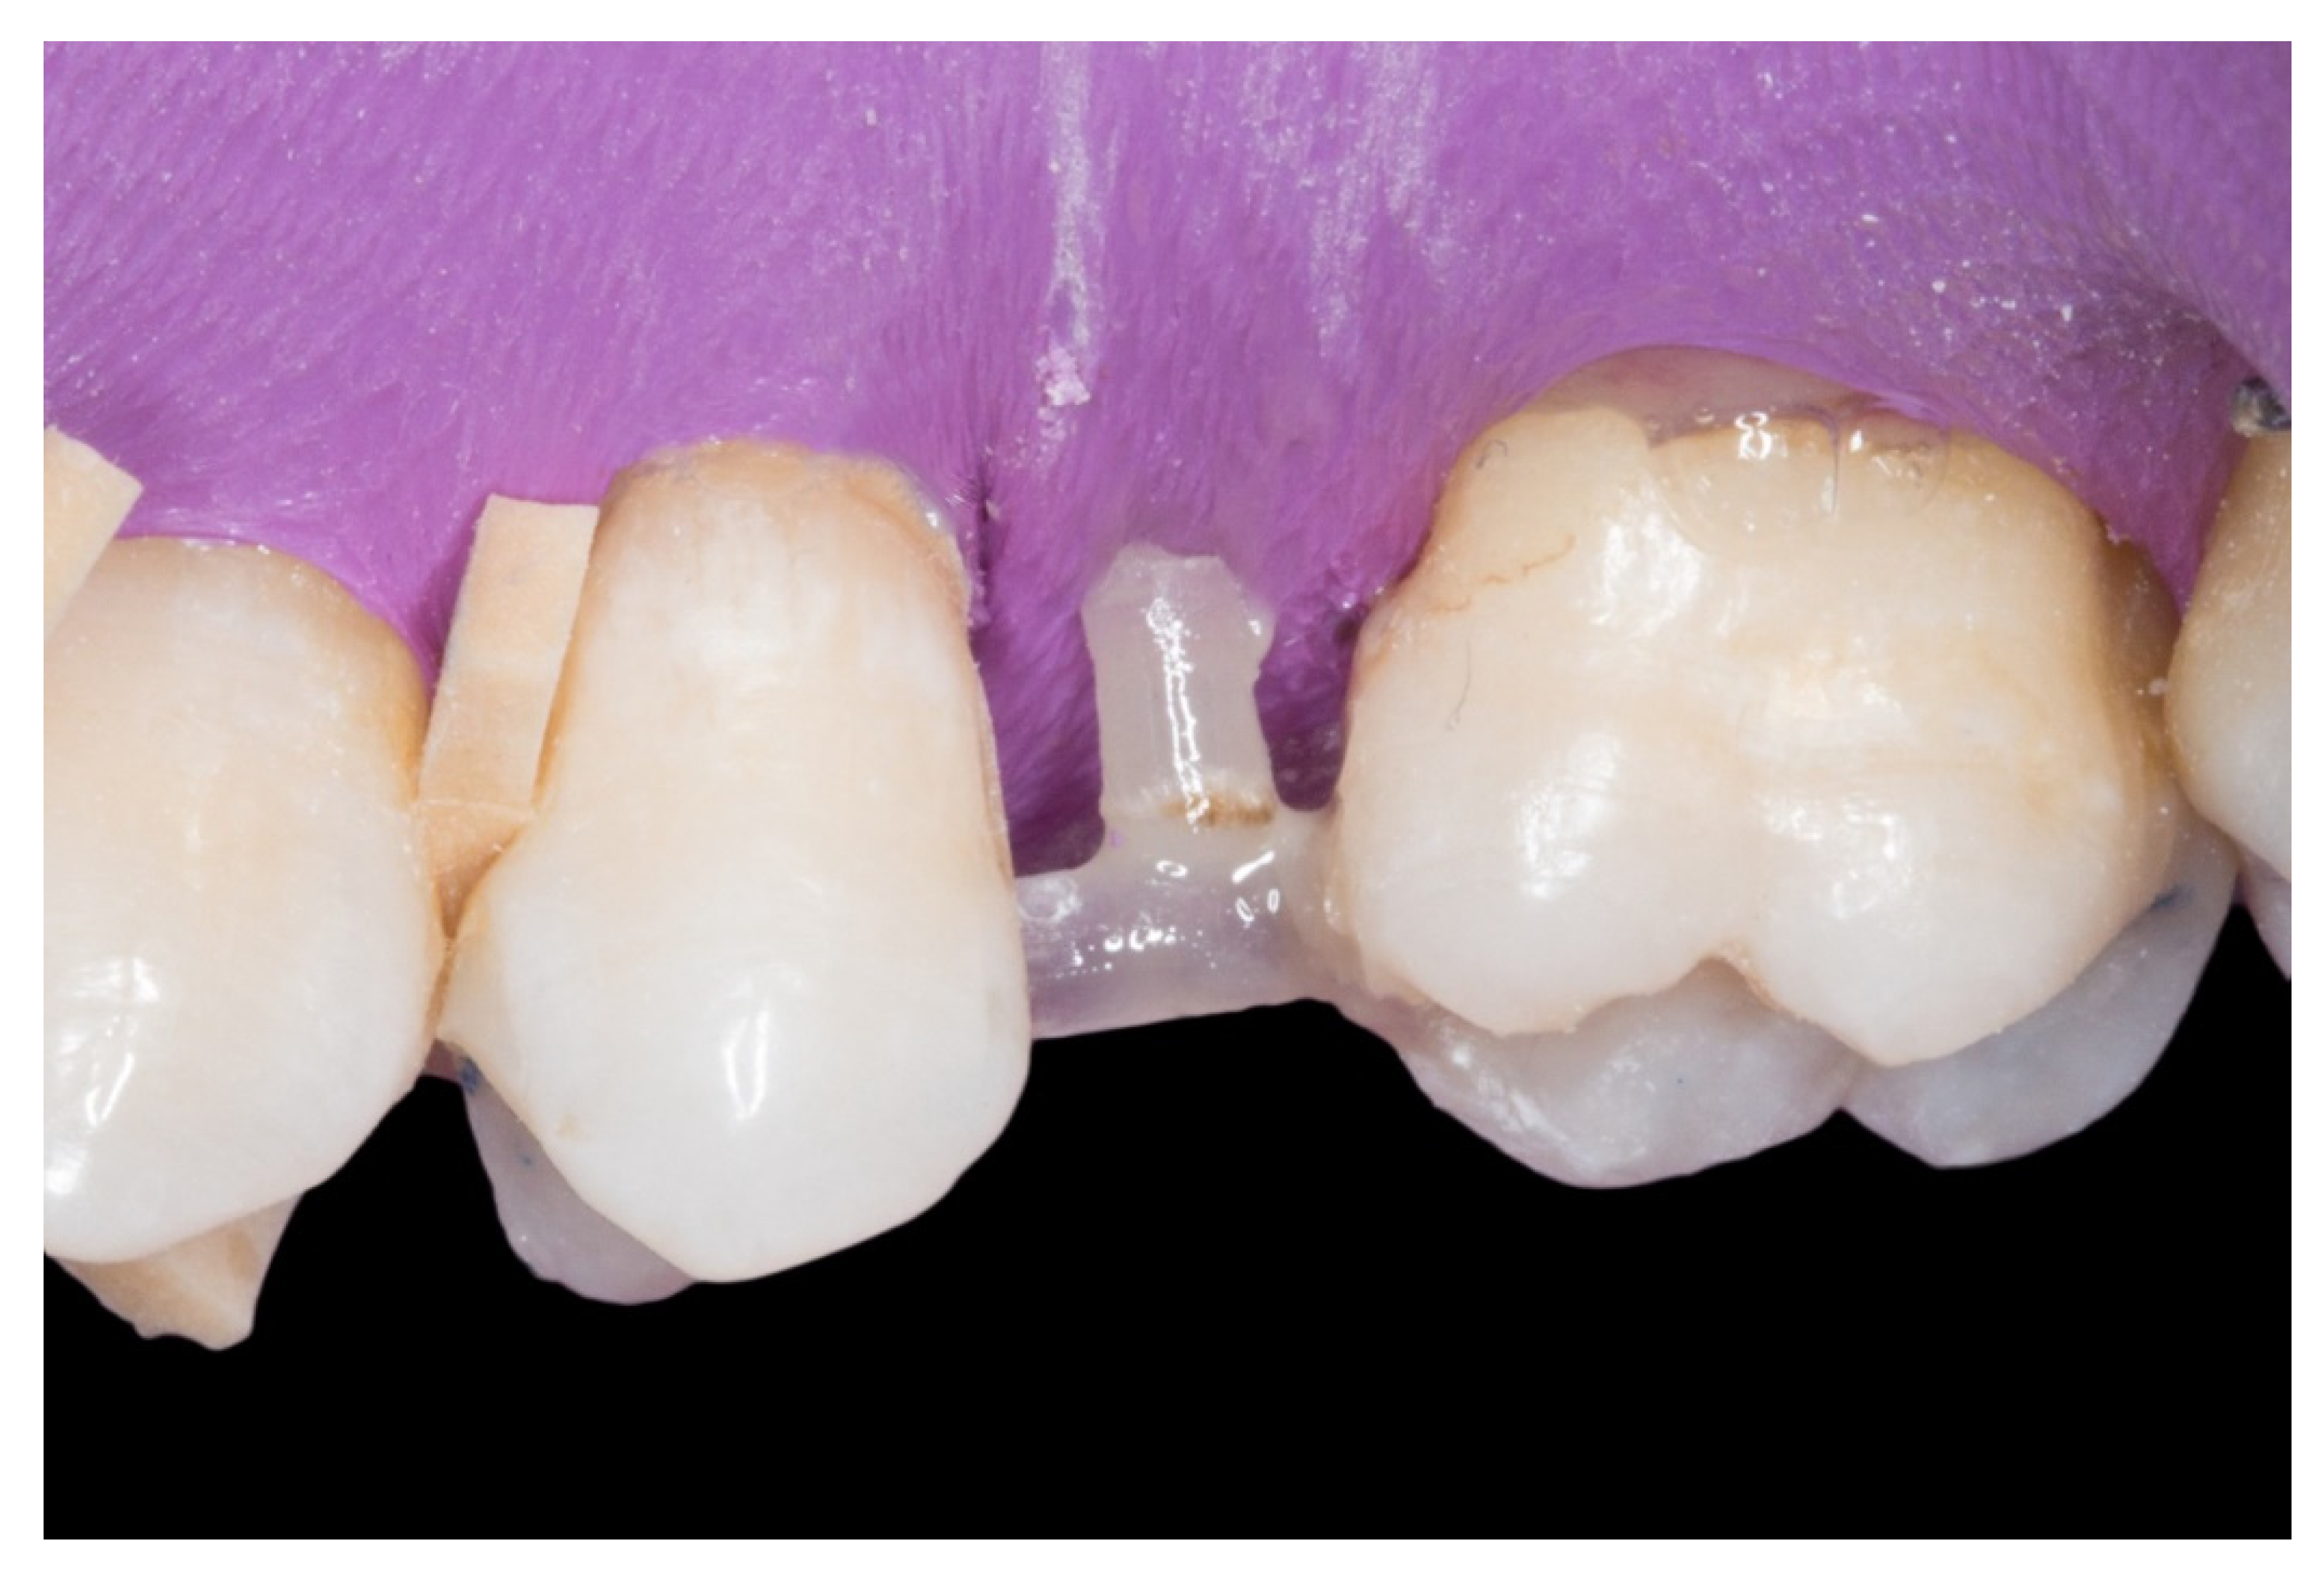

Figure 5.

“T” shape of the fiber-reinforced composite bridge.

4. Afterwards, the pontic core was reinforced with a vertical pin fiberglass structure, which was followed by the same adhesion process mentioned above, obtaining a “T” shape (Figure 5).